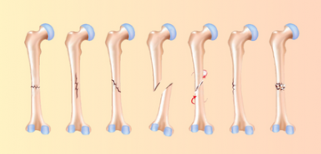

創傷康復:5種天然方法促進骨癒合 (by 運動表現物理治療) - more

處理急性骨折 (by 運動表現物理治療) - more

這是骨折嗎? (by 運動表現物理治療) - more

淺談不同種類的骨折 (by 運動表現物理治療) - more